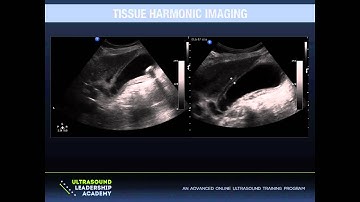

Ultrasound Physics Explained - How does Tissue Harmonic Imaging (THI) work?